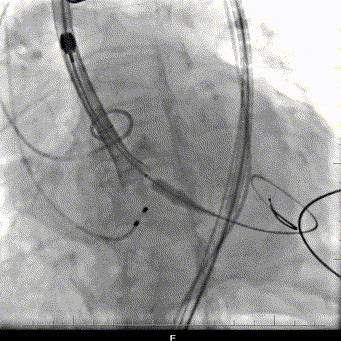

复查造影:瓣膜支架系统膨胀,微量瓣周漏,冠脉显影正常,测量压力阶差5mmHg;术后超声再次评估瓣膜形态,位置可,未见明显反流,手术圆满完成。

术后造影